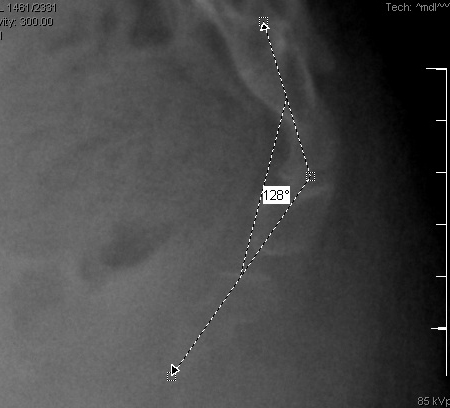

Dynamic lateral sacrococcygeal x-ray in a patient with chronic idiopathic coccygodynia, showing 30° of anterior flexion while standing

From the personal collection of Dr R. Schrot